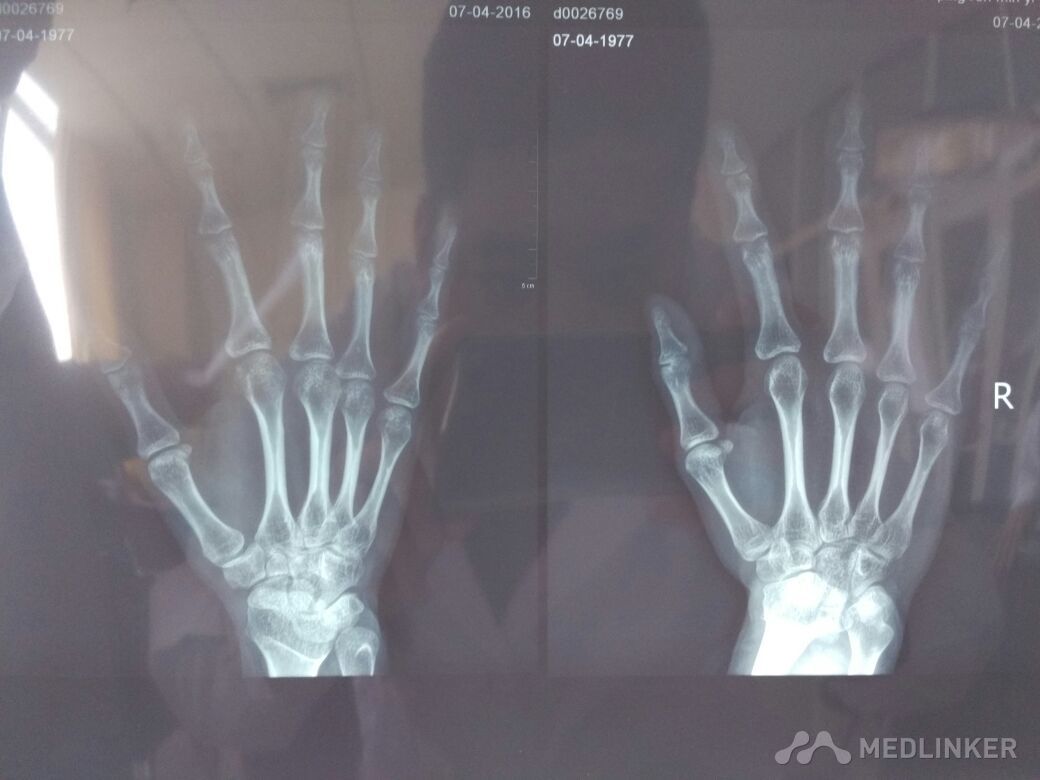

患者女性,40岁,右示指近指间关节疼痛1月余。?

X线提示:骨皮质增厚。各位老师同仁帮忙看看,如何诊治?